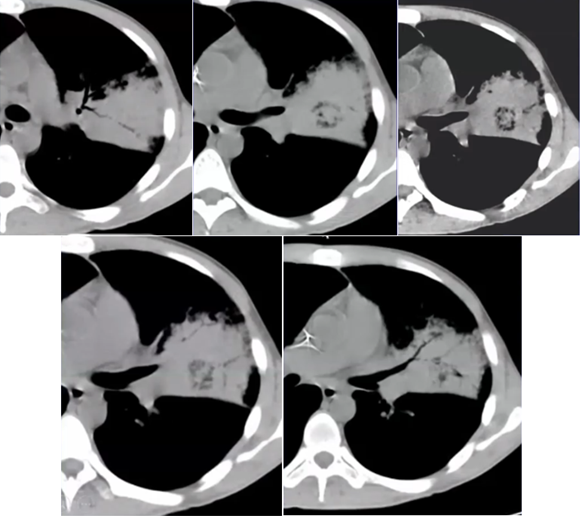

下图为一肿块,周围有晕征,中间有小气泡,增强扫描可见大片坏死,没有强化(图19),这种特征非常像曲霉感染,但最终穿刺病理证实为毛霉感染。其破坏范围更广。临床上,在诊断不清的情况下,一定要做增强扫描,能够帮助确定组织强化的程度。患者出现了胸腔积液,其中的小气泡更大,这是毛霉的特征。

图片

图19  毛霉感染

曲霉的破坏程度与曲霉菌丝生长相对成比例,其破坏范围形成的坏死、空洞及分隔均少于毛霉,而毛霉的破坏力更强。下图是一个结节,周边有晕征,说明病变是血管侵袭性,其中有很多小气泡,没有液平面,说明有菌丝的存在,菌丝固定了坏死物。但纵隔窗看到分隔特别粗大,小气泡特别大,说明坏死占的比例更多,坏死程度更严重,而菌丝的生长与坏死程度不成比例,所以是“坏死多菌丝少”,这是毛霉的特征。而曲霉感染则是“坏死多菌丝多”,坏死物相对固定,小气泡并未形成大的空洞。这也是曲霉和毛霉重要的鉴别点(图22)

图22  毛霉和曲霉感染坏死、空洞的区别

注:A、B为毛霉所致病变,空洞内分隔粗大不均,空洞更大;C为曲霉所致坏死物固定,小气泡多。